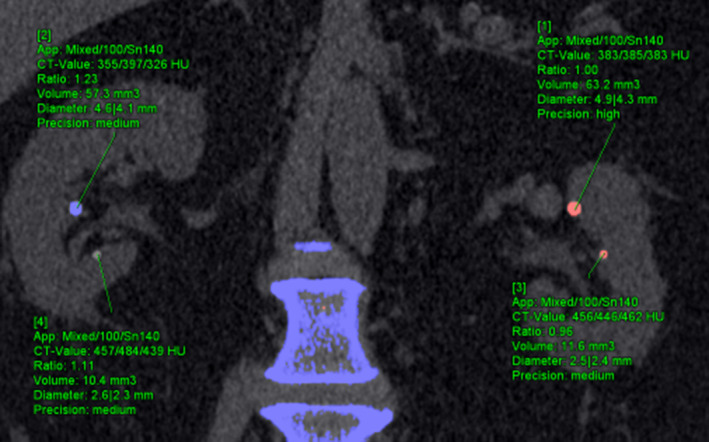

2017年Technical Note: Insertion of digital lesions in the projection domain for dual-source, dual-energy CT

- 肾实质的冠状位插入了四个结石,不同颜色代表不同结石分类